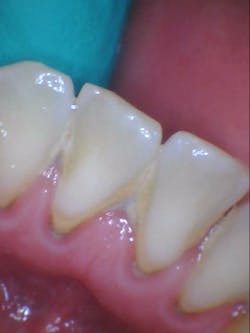

- Additional caries were noted on nos. 10, 11, 14, 26, 27, and 29—primarily facial/buccal caries (figures 3–8)

- In the aforementioned treatment plans, nowhere was it noted or discussed what would happen to the caries on the other teeth aside from nos. 8, 9, and 22.